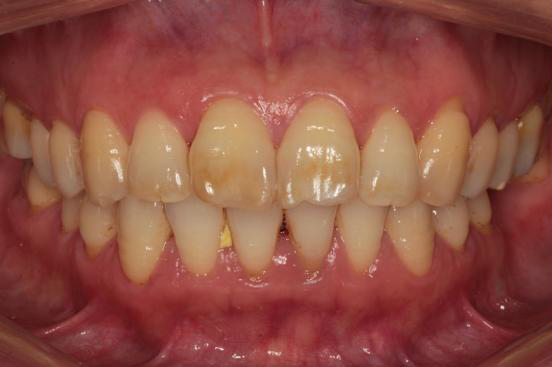

主诉:下颌后牙缺失十年余,要求镶牙 现病史:患者10余年前因牙齿松动于外院拔除下颌双侧后牙(具体不详),偶有咀嚼无力感,现无明显自发痛、冷热刺激痛 既往史:否认高血压、心脏病、糖尿病等重大疾病史,否认重大外伤史、传染病史、严重过敏史。

检查: 口腔卫生条件可,CI=1, DI=1,牙龈无充血肿胀,BOP(-),牙龈退缩约0.5~1mm,未探及深牙周袋,PD:3~4mm;口腔黏膜色性质正常, 舌体大小、形态、活动度正常。 36、47缺失,右侧下颌为游离端缺失,缺牙区近远中间隙及HE龈间隙可;剩余牙槽嵴吸收呈I型,高圆形;35、37牙体未见明显缺损,叩(-),松(-),46近中颊HE面有一大面积磨耗,探(-),叩(-), 松(-),上下前牙切端不同程度磨耗,并有不同程度的黄染,16远中HE面有一大面积黑色色素沉着,探(-),叩(-),松(-)